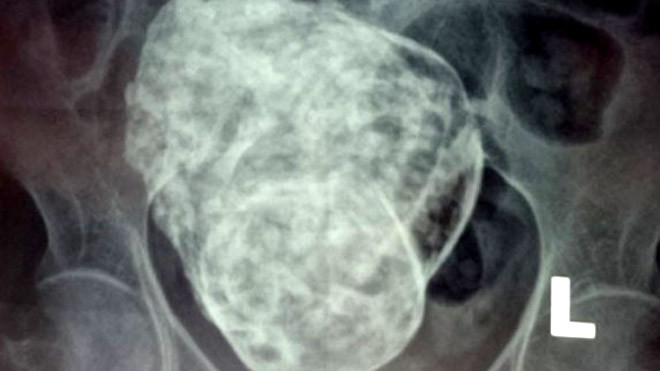

Hình ảnh khối thai đá trong cơ thể bà Sáu

Qua thăm khám và chụp X quang, các bác sĩ phát hiện vùng tiểu khung có khung xương thai nhi (gồm hộp sọ, cột sống, các xương sườn và xương đùi) và chẩn đoán: có thai hết lưu trong ổ bụng.

Qua chụp chiếu, các BS xác định khối u có chiều dài khoảng 15-20cm, chưa rõ cân nặng là bao nhiêu. “Khi sờ nắn, thăm khám thì bà thấy đau tại khu vực có khối u này, còn để bình thường thì không” – BS Quang cho biết thêm.

Khối u cũng chưa xác định được nằm trong hay ngoài tử cung hay tuổi thai là bao nhiêu.